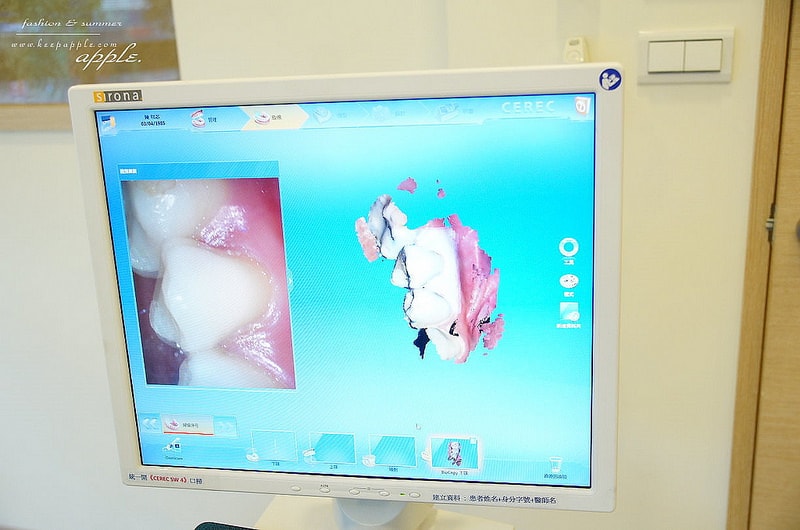

我選的材質是很好的玻璃陶瓷

而且因為是三色的設計仿真度很高

然後就是用超專業的比色儀比對牙齒與假牙的顏色

比對越細,出來的牙齒顏色越接近原本的齒色

看起來更自然~

PS.我的牙齒因為有做過美白比一般人白一點,大概是A1

護士說亞洲平均是A3喔,稍微暗一些

口掃完成之後

資料會傳輸到所有的資料會連動到

>>「3D全瓷冠4軸快速研磨機」上面

當場就可以把假牙研磨出來囉!